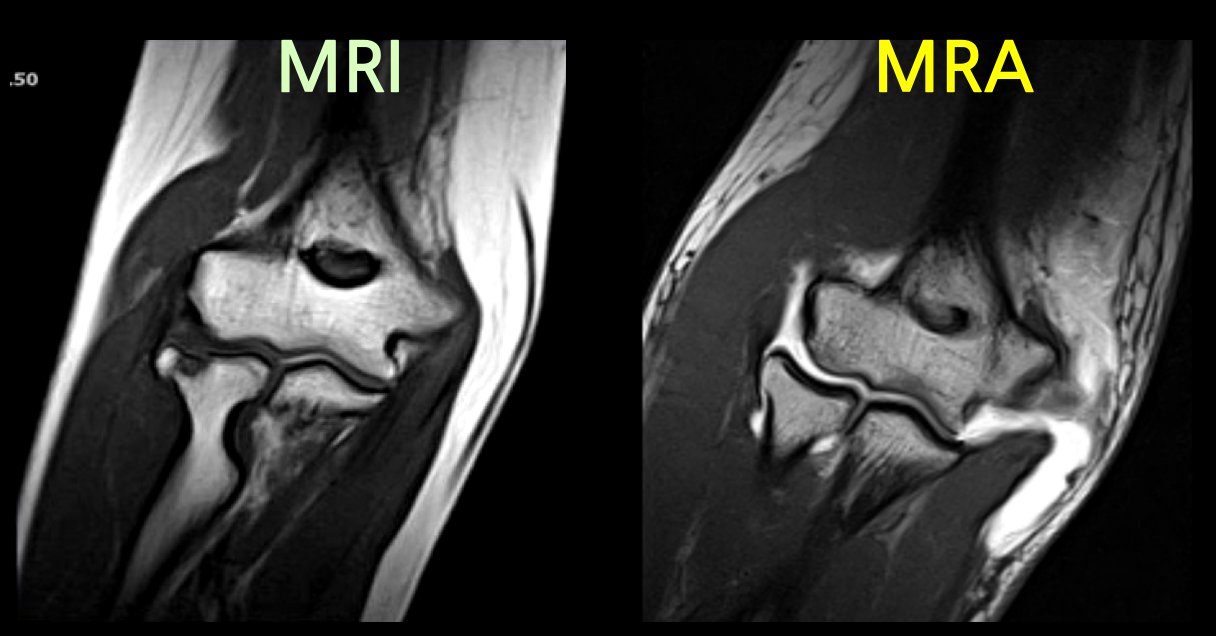

MRA는 MRI와는 다르게 조영제를 사용하며 특히, 같은 부위를 촬영하더라도 조영제 유무에 따라서 촬영된 영상 이미지에 큰 차이가 존재합니다.

작고 좁은 관절에 연부조직을 확인하기 위하여 조영제를 사용하며, 손상여부 및 정도를 확인할 수 있습니다.

정형외과에서 MRA는 어깨, 팔꿈치, 발목과 같은 관절에 적용합니다. 초음파로 확인하기 어려운 관절 전체구조를 확인하고 관절 내 이상소견 및 연부조직 손상여부, 감염등을 확인하는데 큰 도움을 줍니다.

어깨, 팔꿈치, 발목 관절에 조영제를 주입하여 MRI를 촬영하면 조영제가 손상된 틈으로 스며들어 관절 속 미세한 병변까지 진단할 수 있습니다. 이를 관절조영증강 MRI 또는 MRA(Magnetic Resonance Arthrogram)이라고 부릅니다.

- 팔꿈치 : 관절연골 손상, 추벽 등 연부조직 손상